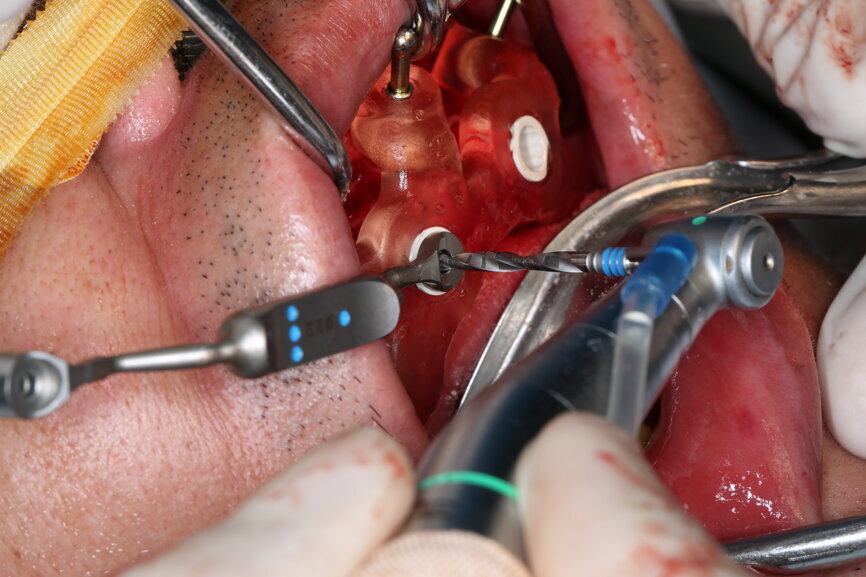

On the day of surgery, we prepared for the surgical protocol provided by the implant planning software, which guided us on the drilling sequence and the use of the appropriate instruments for the implant bed preparation (Figs. 30a & b). After the fixation pins had been allocated, teeth #17, 16, 15, 13, 12, 22, 23 and 24 were atraumatically extracted and alveolectomy was performed using a bone reduction guide (Figs. 31–36). Four implants (Straumann BLX; regular base; diameter: 4.5 mm; length: 12.0 mm) were placed, two straight implants in the anterior and two titled implants in the posterior. All the implants were stabilised to a torque of 50 Ncm (Figs. 37–43), and the SRAs were placed on top. The SRAs on the posterior implants had an angulation of 30° (diameter: 4.6 mm; gingival height: 3.5 mm) and on the anterior implants an angulation of 17° (diameter: 4.6 mm; gingival height: 3.5 mm; Figs. 44 & 45).